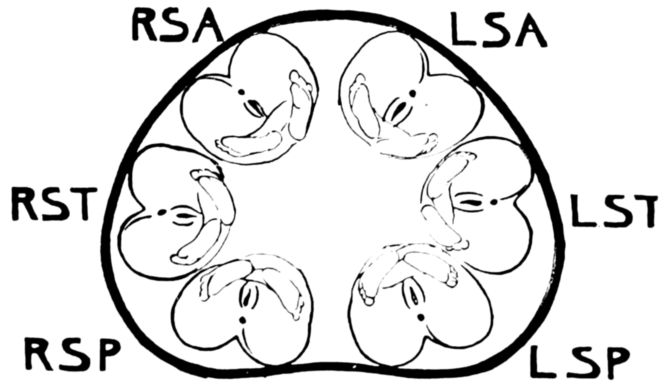

| 54. | Diagram of six positions in a vertex presentation | 222 |

| 55. | Diagram of six positions in a face presentation | 223 |

| 56. | Diagram of six positions in a breech presentation | 223 |

| 61. | Diagrams showing positions of nurse’s hands in four maneuvers of abdominal palpation | 229 |